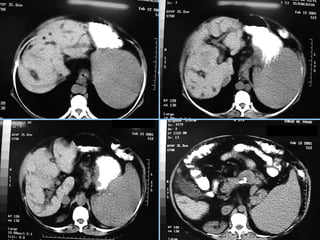

Hemangioma

 Fase art.      Fase portal    Fase tardia

 S/C              Fase art.

 Fase portal      Fase tardia

 S/C      Fase art.    Fase tardia